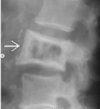

Fratura compressiva da coluna lombar

Causa achatamento do corpo e acunhamento geralmente anterior.

Tipo mais comum de fratura da coluna lombar

Estável.

Mecanismo flexão anterior ou lateral